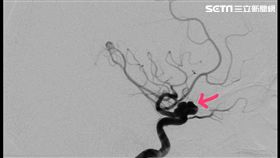

頭爆痛?你恐跨腦動脈瘤的生死分界線

已八十高齡曾老太太因失智問題前往安南醫院神經內科尋求...